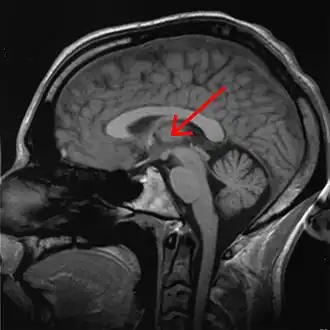

The effects of sleep deprivation on cognitive performance have been studied through the use of parametric visual attention tasks. Functional magnetic resonance imaging of participants' brains who were involved in ball-tracking tasks of various difficulty levels were obtained. These images were taken during rested wakefulness and again after one night of sleep deprivation. The thalamus is more highly activated when accompanied by sleep deprivation—than when the subject is in a state of rested wakefulness. Contrarily, the thalamus is more highly activated during difficult tasks accompanied by rested wakefulness, but not during a state of sleep deprivation. Researchers propose that the thalamic resources, which are normally activated during difficult tasks, are being activated in an attempt to maintain alertness during states of sleep deprivation. An increase in thalamic activation is related to a decrease in the parietal, prefrontal and cingulate cortex activation, resulting in the overall impairment of attentional networks, which are necessary for visuospatial attention performance.[12]

PET scans shows global decrease in glucose metabolism in response to sleep deprivation. As subjects become increasingly impaired on working memory tasks, a more specific decrease of glucose occurs in the thalamus, prefrontal cortex and posterior parietal cortex.[42]

fMRI scans following brief sleep deprivation (24 hours or less) show increases in thalamic activation. Verbal working memory tasks normally cause increases in left temporal lobe activity. After 35 hours come noted decreases in temporal lobe activation and increases in parietal lobe activation.[42]

Lack of sleep changes how genes are expressed and interferes with neurobiological functions that are necessary for cognitive function. Research indicates a decline in the expression of proteins that are essential for memory consolidation and synaptic plasticity, including CREB and PKCγ. These molecular abnormalities damage the cerebellum and hippocampus, which results in deficiencies in long-term memory functions and spatial working memory. Chronic sleep deprivation also raises the brain's amyloid-beta aggregation, which is linked to neurodegenerative diseases like Alzheimer's. Impaired clearance mechanisms during reduced sleep worsen this neurotoxic environment. Neuroimaging studies also show a shift of cognitive resources, which decreases activation in the prefrontal cortex and parietal lobes and increases activation in areas like the thalamus. However, this compensating strategy is not enough to sustain the best possible cognitive function throughout extended periods of wakefulness.[61][62]